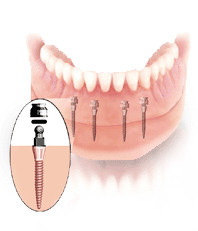

Mini-Implantate sind eine schnelle, kostengünstige Alternative für Patienten, die den Sitz ihrer Prothese verbessern wollen, allerdings Aufwand und Kosten für herkömmliche Implantate scheuen.

Diese Art der Sofortversorgung bedarf im Unterkiefer mindestens 4 und im Oberkiefer, aufgrund der weicheren Knochenstruktur, mindestens 6 Implantate. Von entscheidender Bedeutung ist hierbei, dass sich die Implantate stabil im Kiefer verankern lassen. Durch ihren schmalen Aufbau kann der Zahnarzt sie auch bei schwierigen Knochensituationen setzen, für die herkömmliche Implantate erst einen umfangreichen Aufbau der Knochen erforderten. Mit den Mini-Dental-Implantaten von 3M Espe schaffen wir es in ca. zwei Stunden, dass Ihre Prothese auf Dauer stabil sitzt.

Mini-Implantate eignen sich besonders für die Fixierung von herausnehmbarem Zahnersatz, insbesondere in engen Bereichen oder bei minimalinvasiven Ansprüchen. Klassische Implantate sind dagegen ideal für dauerhaften, festsitzenden Zahnersatz wie Kronen oder Brücken. Sie bieten langfristige Stabilität, erfordern jedoch eine umfangreichere Vorbereitung.

Da sich die vorhandene Zahnprothese in vielen Fällen weiterverwenden lässt, ist eine Neuanfertigung häufig nicht notwendig. Dadurch entfallen hohe Laborkosten. Eine Stabilisierung einer Prothese ist auf diese Weise für 2.000 bis 3.000 € zu realisieren.

In unserer Zahnarztpraxis in Braunschweig nutzt Zahnarzt Dr. Rüffert das Mini-Implantat der Firma 3M Espe (vormals IMTEC Sendax MDI-System (Mini-Dental-Implantat)). Dieses besitzt die amerikanische FDA-Zulassung und die europäische Medizinprodukt-Zulassung für eine Langzeitstabilisierung von Zahnersatz.